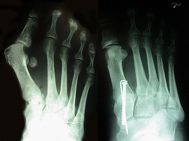

Wegen der häufigen „Begleitdeformitäten“ einer Hallux valgus-Fehlstellung kommen zahlreiche unterschiedliche Operationsmethoden zur Anwendung. Sie unterscheiden sich teilweise erheblich im zeitlichen und materiellen Aufwand sowie im Schwierigkeitsgrad. Das Verfahren, das mit dem kleinsten operativen Aufwand ein ungestörtes, schmerzfreies Gehen bei einem optisch ansprechenden Ergebnis verspricht, wird in einem ausführlichen Gespräch mit dem Patienten ermittelt. Dabei werden die Beschwerden, das Ausmaß der Fehlstellung, das Ergebnis der Röntgenuntersuchung, die Nachbehandlungsdauer und das Alter des Patienten berücksichtigt.

Beispiel einer Hallux valgus-Korrekturoperation vor (links) und nach dem operativen Eingriff (rechts)

Beispiel einer Hallux valgus-Korrekturoperation vor (oben) und nach dem operativen Eingriff (unten)